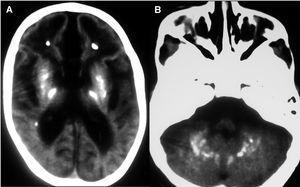

Evolutivamente se observó escaso incremento del perímetro craneal, desconexión medioambiental, desarrollo de tetraplejía espástica, control cefálico deficiente e hipertonía generalizada. Se realizó nueva neuroimagen (tomografía computarizada [TC] y resonancia magnética [RM]), donde se observaron extensas calcificaciones bilaterales cerebrales supratentoriales e infratentoriales, afectándose ambos hemisferios cerebelosos, núcleos basales y zona periventricular, ausencia de mielinización, lisencefalia frontal e intensa atrofia corticosubcortical (figs. 1 y 2). Se realizó biopsia muscular del vasto externo, cuyo estudio anatomopatológico y enzimático de la cadena respiratoria mitocondrial fue normal. Se demostró elevación del IFN-α en plasma y más marcado en LCR (12 y 200 U/ml, respectivamente, valores normales < 2 U/ml). El paciente desarrolló epilepsia y presentó nula adquisición psicomotora, y murió a los 27 meses de edad.

Figura 2.A)TC cerebral. Extensas calcificaciones bilaterales cerebrales que afectan núcleos basales y zona periventricular.B)TC cerebral. Calcificaciones en hemisferios cerebelosos.